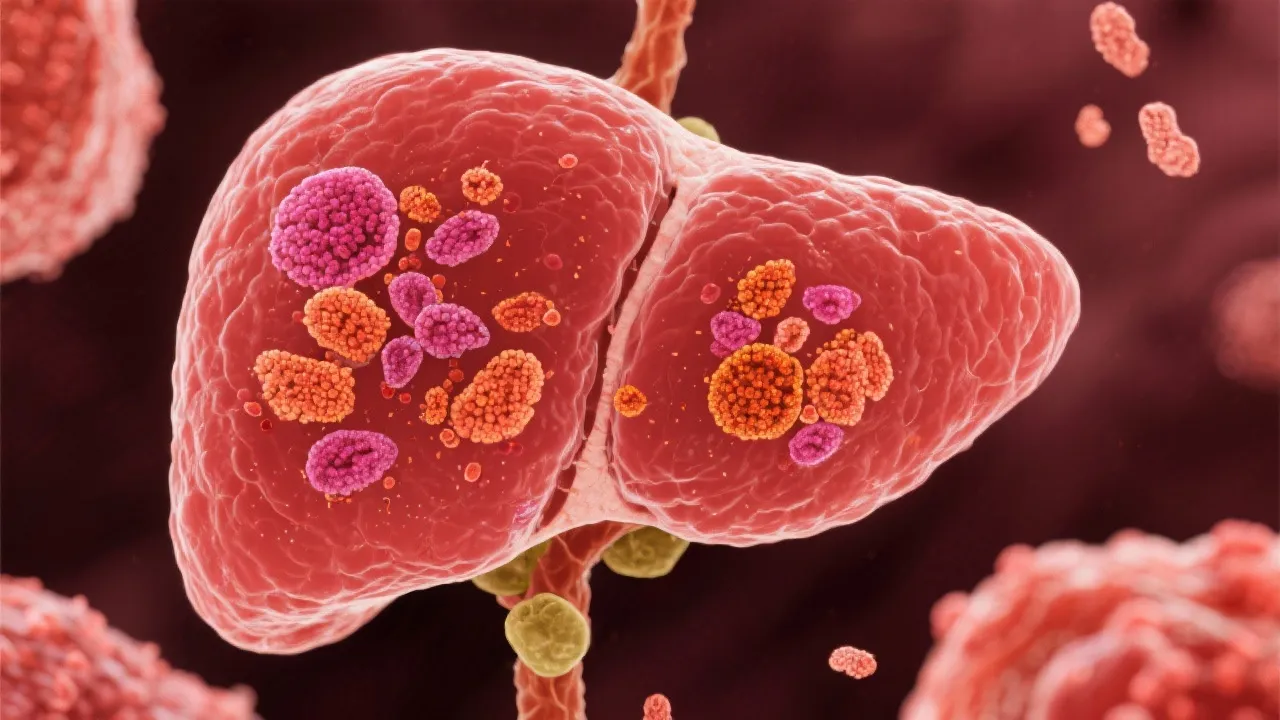

Understanding the Hepatitis B Virus

Understanding HBV Treatment and Advances

Understanding Hepatitis B Virus

Understanding Hepatitis B Virus

Understanding HBV: A Comprehensive Guide

Understanding HBV and Treatment Options

Understanding Hepatitis B Virus

Understanding the Hepatitis B Virus

Understanding Hepatitis B Virus

Understanding HBV: An In-depth Analysis

Understanding the Impact of HBV

Understanding Hepatitis B Virus